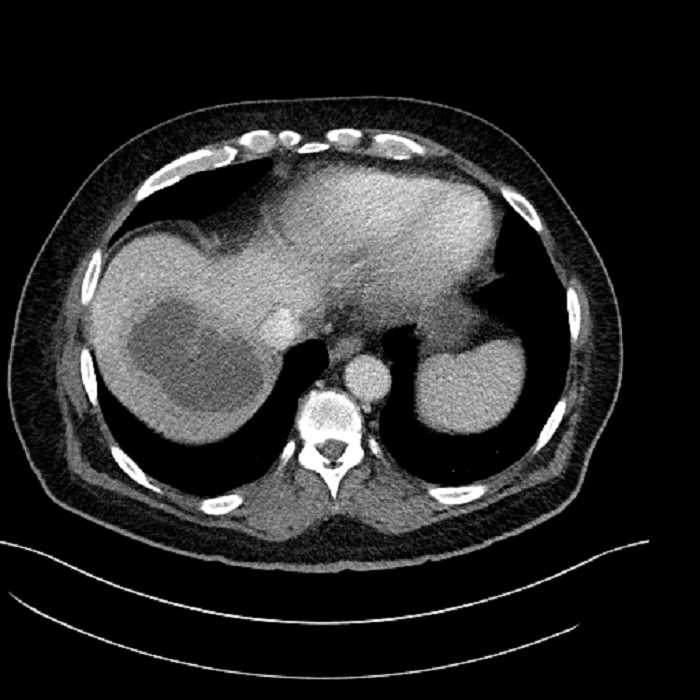

• Large fluid density structure in hepatic segments 7 and 8 measuring 10 x 7 x 7 cm with internal septation and circumferential ill-defined low density compatible with edema

• Peripherally enhancing subcapsular collections along the anterior margin of the left hepatic lobe measuring 3 x 1 cm and 2 x 1 cm

Acute sigmoid diverticulitis complicated by a small contained perforation and a large abscess in the right hepatic lobe. Additional small subcapsular abscesses along the anterior margin of the left hepatic lobe.

• The classic CT imaging appearance is a double target sign with internal low density surrounded by an internal enhancing rim (capsule) and a low density external rim (edema)

Hepatic abscess showing the double target sign with low density internally surrounded by a thin inner enhancing rim (red arrow) and ill-defined outer low density rim (yellow arrow). Blue arrow indicates an internal septation. Red arrows: additional smaller subcapsular abscesses. Red arrow: focal contained perforation associated with diverticulitis.